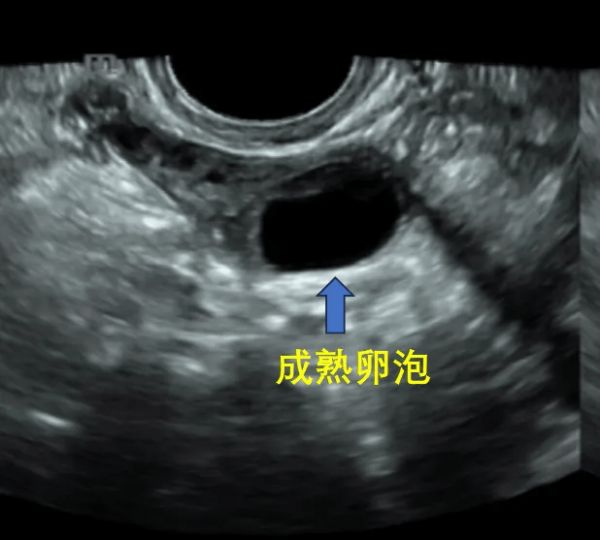

卵泡>18 mm时:为成熟卵泡,需要每日监测直至卵泡排出,也可在此时进行诱导排卵。

当卵泡直径达18mm以上,部分卵泡内壁可见半月形的突起,属于卵泡成熟的征象,超声监测排卵征象:①成熟卵泡明显缩小,由饱满变塌陷或消失;②卵泡张力欠佳,形状不规则,内部结构模糊,卵泡壁呈锯齿状改变。